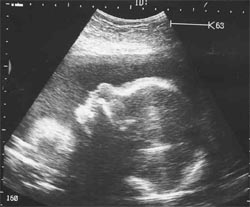

Что представляет собой плод на 29 неделе развития

К 29 неделе плод достигает около 37 сантиметров в длину и весит уже приблизительно 1250 грамм.

Голова и тело становятся все более и более пропорциональными.

В целом, тело ребенка становится пухлее за счет нарастания жировых клеток. Это необходимо для регулировки тепла.

В часы бодрствования малыш постоянно вертится, и без специальных аппаратов становится понятно, принял ли он правильное положение головой вниз. Там, где толчки почти не слышны и есть голова, ведь ручками и ножками он постоянно упирается в стенки матки.